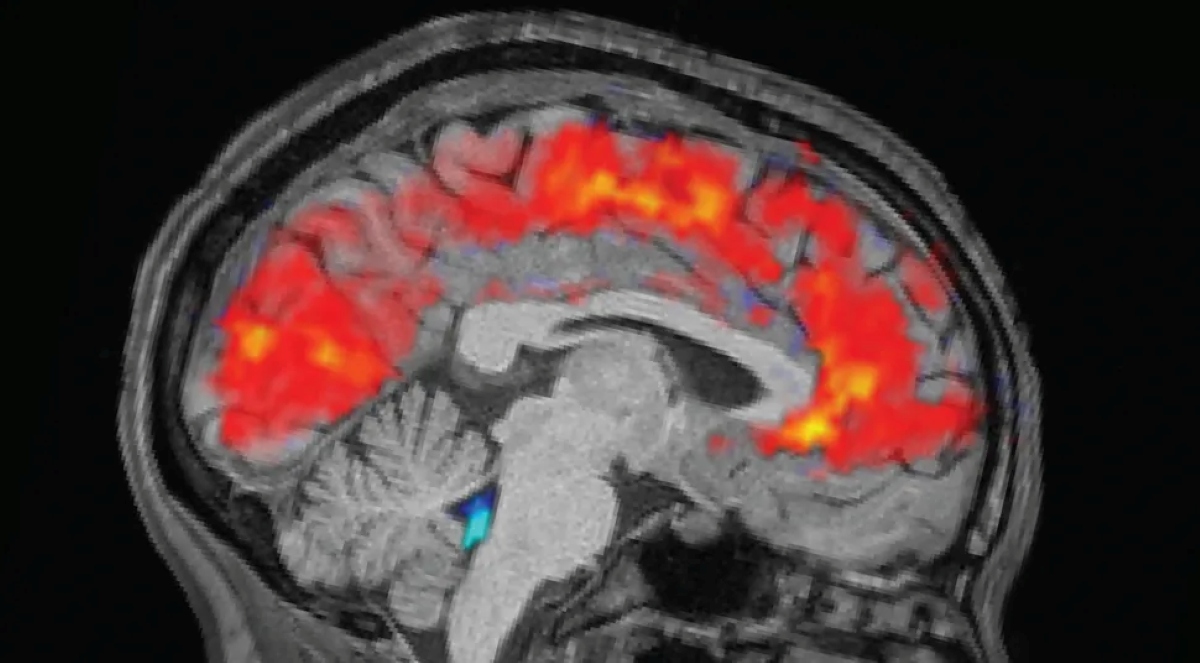

بیخوابی همیشه مانند سایهای سنگین بر ذهن انسان میافتد؛ سایهای که تمرکز را میبلعد و رشتهٔ فکر را چون نخ پوسیده پاره میکند. پژوهش تازهای که در مجلۀ Nature Neuroscience منتشر شده، پردهای تازه از این تجربه گشوده و نشان داده است که مغزِ بیخواب، وارد حالتی میشود که معمولاً فقط در خواب عمیق رخ میدهد.

در این وضعیت، مایع مغزی–نخاعی، که همچون جویبار محافظ مغز جریان دارد، ناگهان از بافت مغز بیرون میرود و پس از چند لحظه بازمیگردد؛ رفتوبرگشتی که بخشی از فرایند پاکسازی مواد زائد است. این تغییر تنها به مایع محدود نمیشود. همزمان، جریان خون در بخشهای مختلف مغز دگرگون میشود و مردمک چشم، همان گشودۀ ظریف جهانبینی ما، تغییر اندازه میدهد.

نکتۀ مهم این پژوهش، هماهنگی شگفتانگیز این سه رخداد است. چیزهایی که پیشتر جداگانه بررسی میشدند، اکنون همچون سه ساز در یک ارکستر عصبی، همصدا عمل میکنند و لحظههای «خاموشی ذهن» پس از بیخوابی را پدید میآورند.